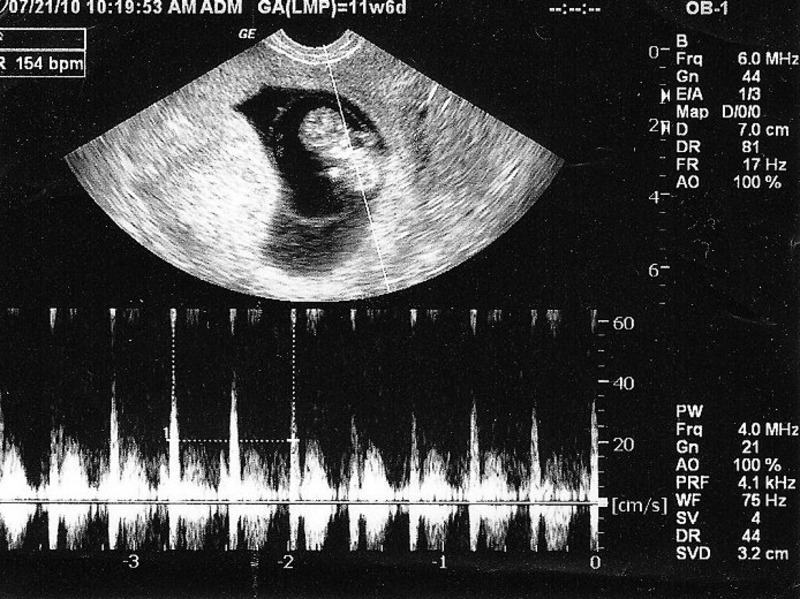

Thông qua siêu âm đo CRL trong giai đoạn 6-14 tuần, bác sĩ có thể kết hợp nghe nhịp tim thai để đánh giá sức khỏe phôi thai. Một nhịp tim đều và mạnh cho thấy thai nhi phát triển bình thường, trong khi bất thường về CRL có thể cảnh báo nguy cơ sảy thai. Bên cạnh đó, chỉ số MSD (Mean Sac Diameter – đường kính trung bình túi thai) cũng được so sánh với CRL để chẩn đoán nguy cơ này. Nếu hiệu số giữa MSD và CRL nhỏ hơn 5mm, thai phụ cần theo dõi sát vì khả năng sảy thai tăng cao. Đây là dấu hiệu cảnh báo quan trọng trong giai đoạn thai sớm.